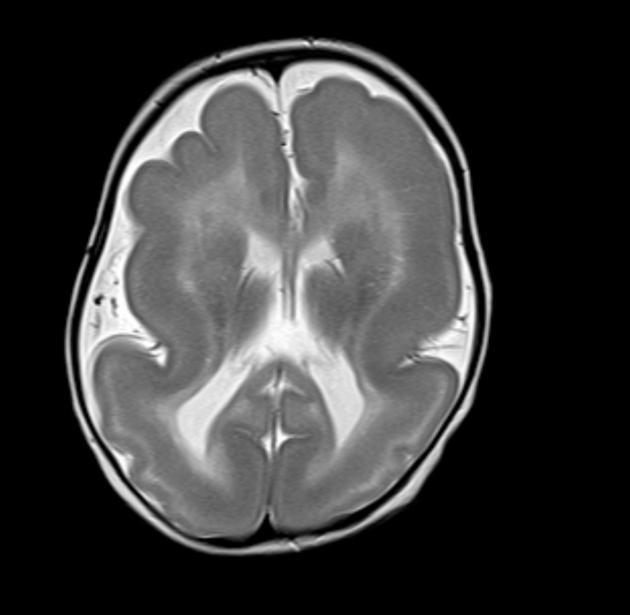

Diagnosis?

Lissencephaly type 1.

Lissencephaly type 1 (classic):

Imaging features?

Presentation?

Syndrome association?

Imaging- brain has few shallow sulci and shallow Sylvian fissures, “hour glass” appearance. Smooth, thickened cortex (4 layers, normal is 6), may have subcortical band heterotopia.

Presentation- Marked hypotonia and paucity of movements, difficulty feeding. Develop microcephaly (normal at birth). Seizures.

May be isolated or part of a syndrome, most commonly Miller-Dieker syndrome.